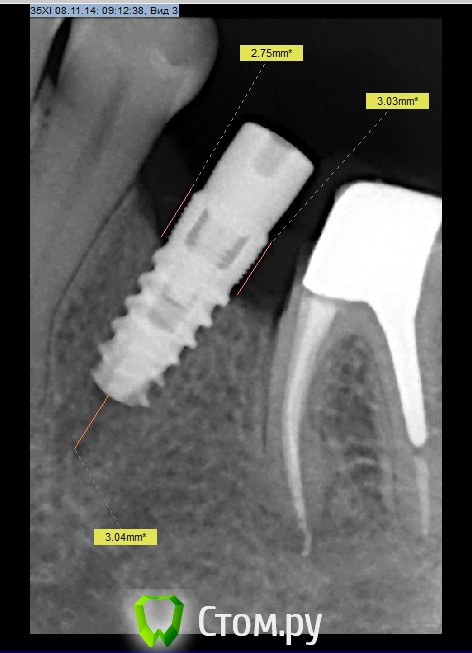

Рустам Опубликовано 11 ноября, 2014 Поделиться Опубликовано 11 ноября, 2014 Интегрированный имплантат MIS. Как бы поступили в данной ситуации коллеги. В полости рта имплантат на уровне десны, вестибулярно выше десны на 0.5 мм.Отправил переустановить. 1 Ссылка на комментарий

Рустам Опубликовано 11 ноября, 2014 Автор Поделиться Опубликовано 11 ноября, 2014 Хирург контрольный снимок не делал что ли.. судя по снимку видно, что ложе под имплантат не полностью заполнено. Мне интересно, как пациенту преподнесли необходимость повтороной имплантации?А если бы пациент пришел уже с интегрированным имплантатом через 3 месяца..представляю себе реакцию такого пациента ))))Хирург делал снимок после постановки имплантата,имплантат был поставлен выше кости на 2 мм, внятного объяснения почему не вровень с костью не получил, хотя условия хорошие.Вообще пациент пришел ко мне спустя 3 месяца с уже интегрированым имплантатом)))Сказал хирургу чтобы сама объяснила пациенту о необходимости переустановки имплантата. Ссылка на комментарий